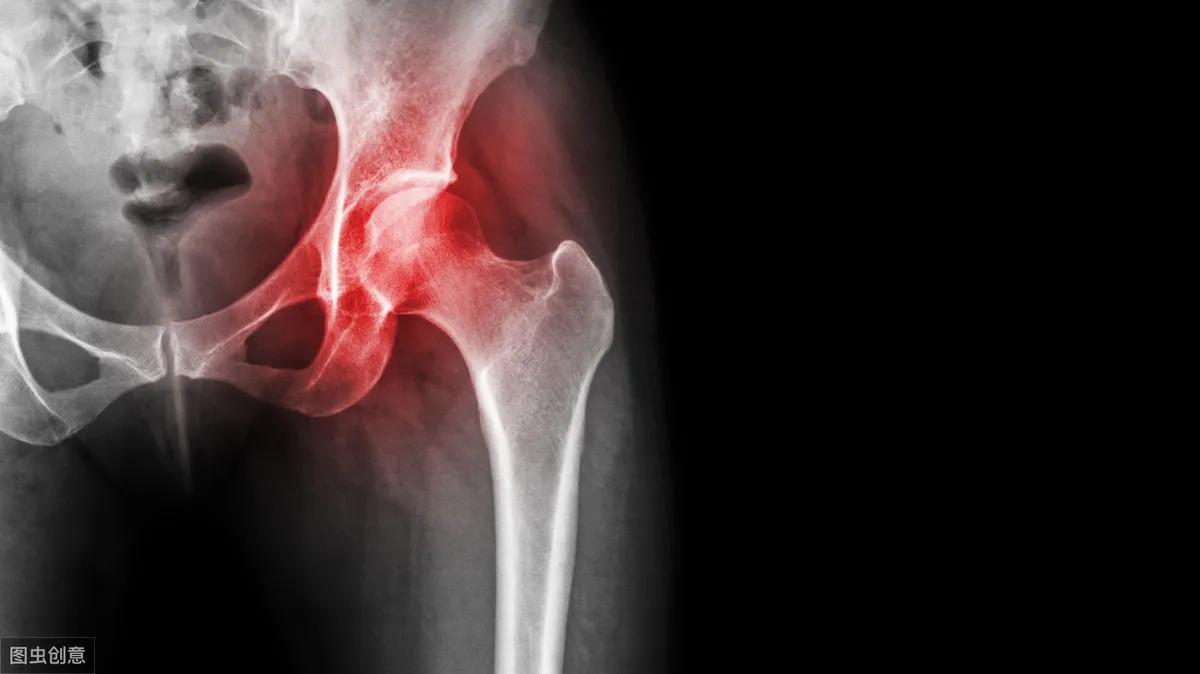

髋部在哪?髋部就是我们平时所说的「胯部」,髋关节一边是股骨,一边是盆骨,股骨头和髋臼构成了髋关节,它承载了人体上半身的重量,影响人的站立和行走。